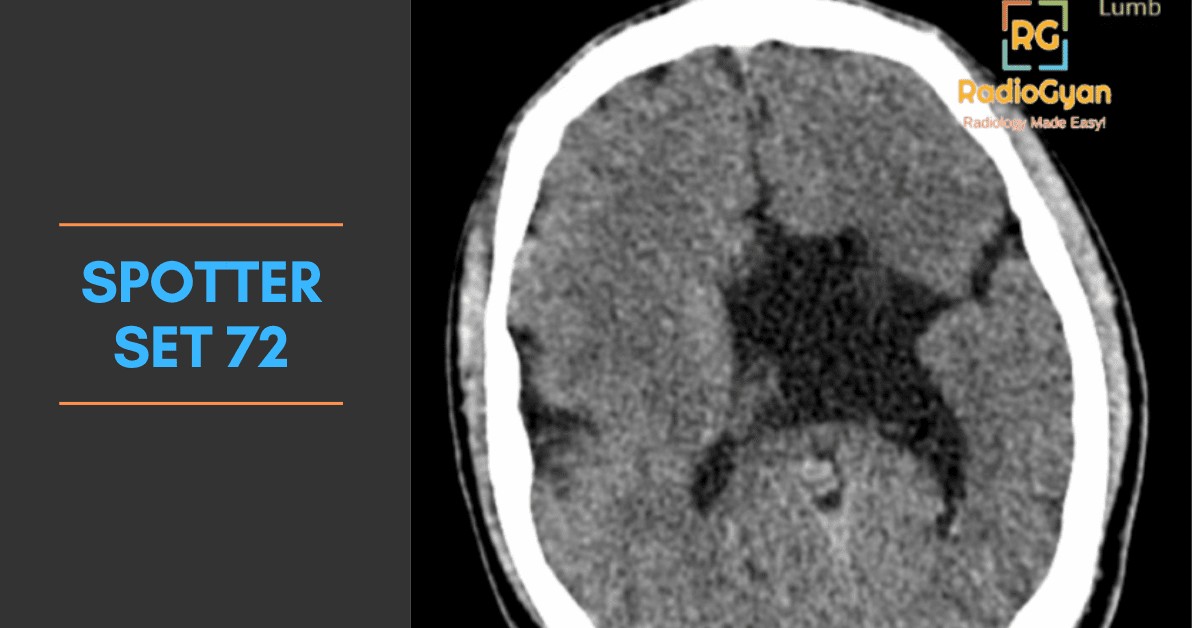

Explore high-yield radiology spotters with detailed explanations and case discussions to enhance your diagnostic skills at RadioGyan.com.